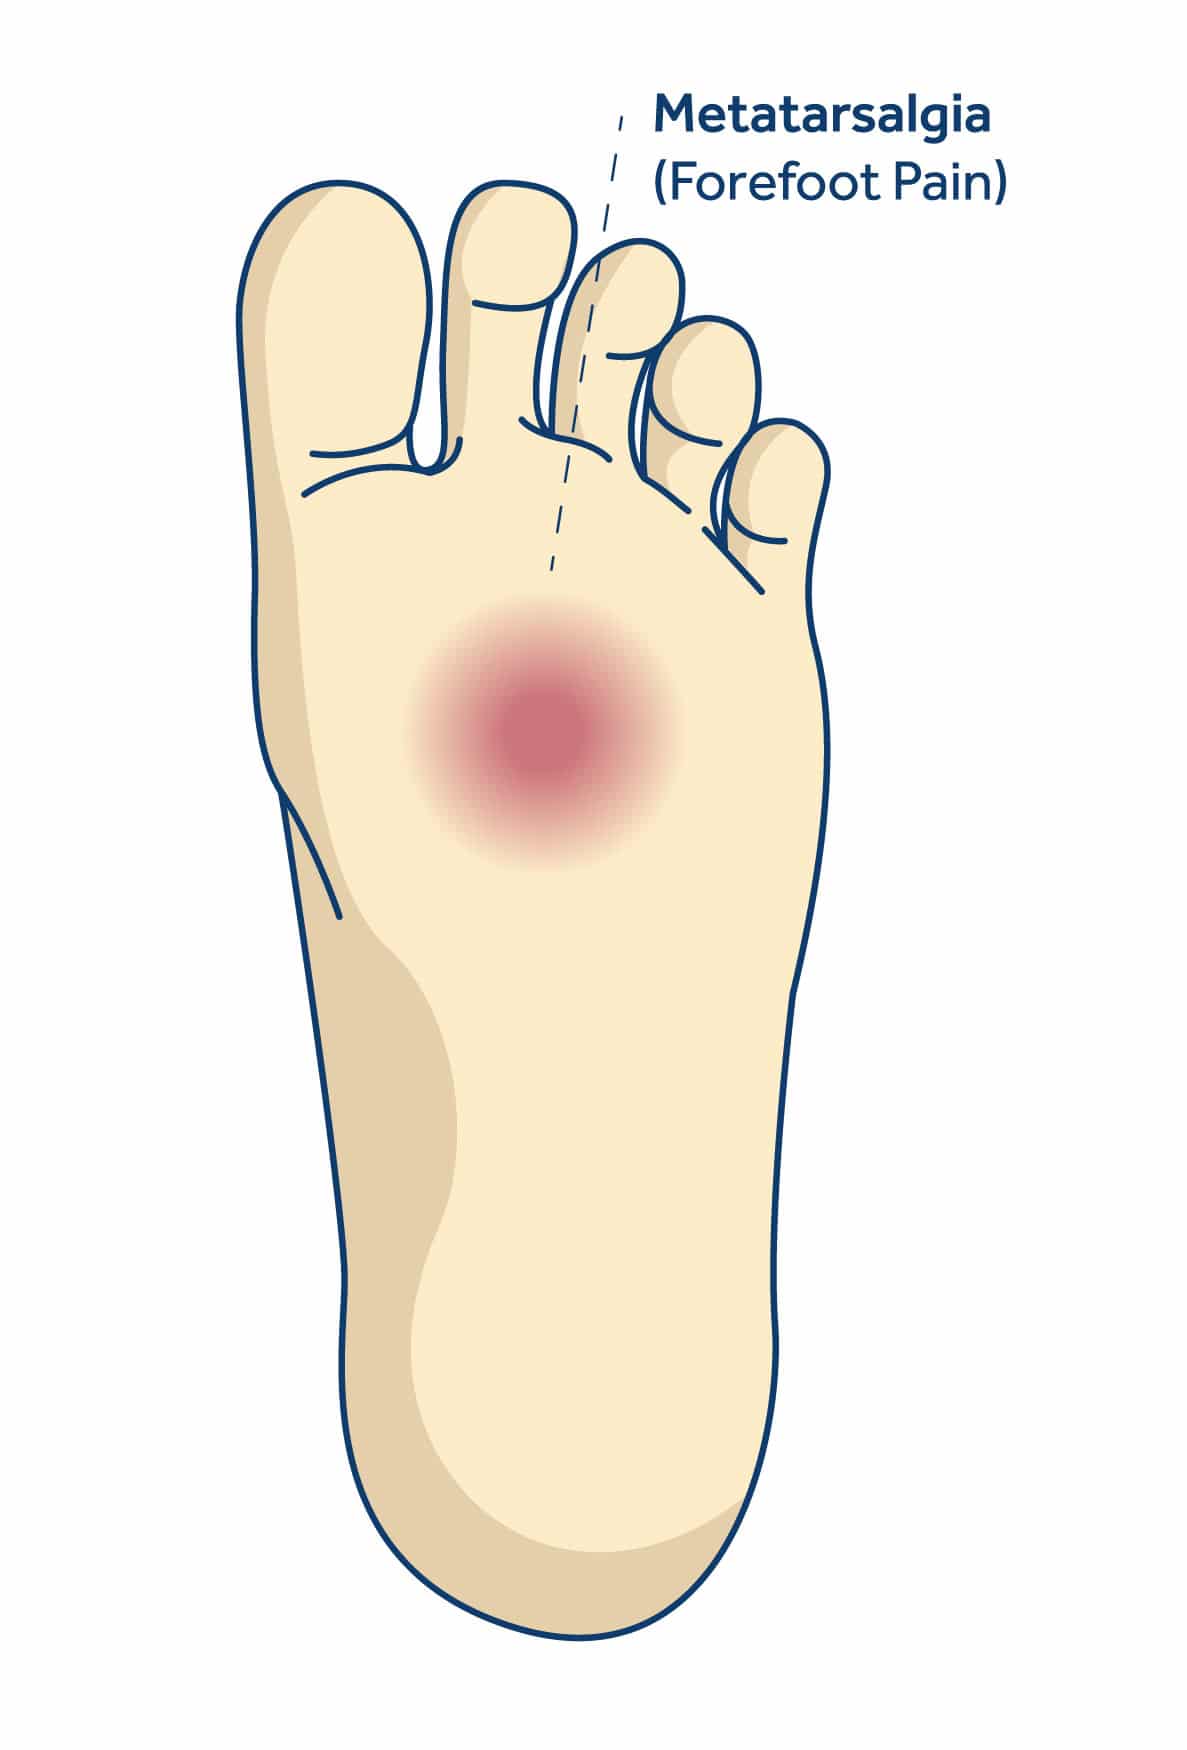

Forefoot pain

Metatarsalgia is pain and inflammation in the ball of your foot. Potential causes of the condition include foot deformities, inflammatory issues and wearing ill-fitting shoes. The pain of metatarsalgia typically centers under one or more of the five bones at the bases of your toes, over the metatarsal heads.

Metatarsalgia has a number of different causes, including:

Metatarsalgia symptoms can come on quickly or develop over time. They include: